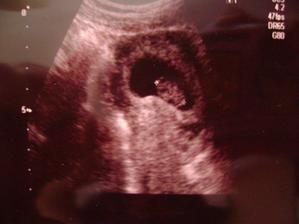

@zuzulaxx🙂 hm...dobrá otázka🙂bola som umelo oplodnená.odo dna vkladu embrií po prvé sono(fotka)sú to 4 týždne,doktor mi ale povedal že som v 5 týždni,ale od poslednej menštruácie je to 7 týždnov....takže som z toho úplne mimo🙂)))))))))))))Vidím,že sme na tom podobne🙂))))))))))))gratulujem🙂